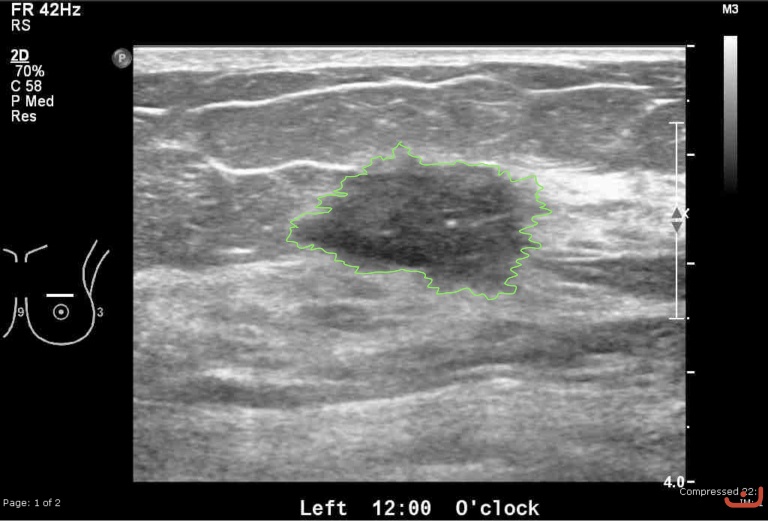

Case 32-G1

Malignant solid mass

Friday, 22 May 2015

184.01 KB (768 x 521 px)